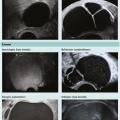

L’imagerie des lésions ovariennes repose sur le triptyque : échographie endovaginale avec Doppler, imagerie par résonance mag­nétique (IRM) et tomodensitométrie (TDM). Si l’échographie reste l’examen de première intention, en fonction de la question posée et du type de lésion ­découverte, la réalisation d’une IRM pelvienne ou d…